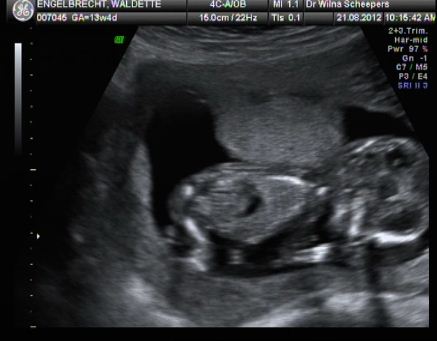

Dr Scheepers:

Die rede dat Waldette Dr Scheepers toe gegaan het is om in meer detail te sien vir dow sindroom en ander issues.

Ongelukkig was baba nie gewillig om reg te le nie en die gesiggie was toe met die plasenta.

Maar hier is van die pics en video.

Frieken, Slaap op die maag. But heart beat was there.

Hier le die baba en slaap. WT$#^$

Guys, do not feel bad. I also cannot make out the pic.

Somewhere you will see feet, hands and stuff and only a Dr can say what is what.